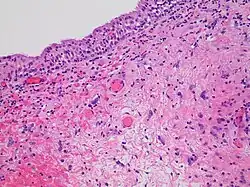

Histopathology of radiation cystitis, including atypical stromal cells ("radiation fibroblasts")

The gastrointestinal tract can be damaged following abdominal and pelvic radiotherapy.[42] Atrophy, fibrosis and vascular changes produce malabsorption, diarrhea, steatorrhea and bleeding with bile acid diarrhea and vitamin B12 malabsorption commonly found due to ileal involvement. Pelvic radiation disease includes radiation proctitis, producing bleeding, diarrhoea and urgency,[43] and can also cause radiation cystitis when the bladder is affected.